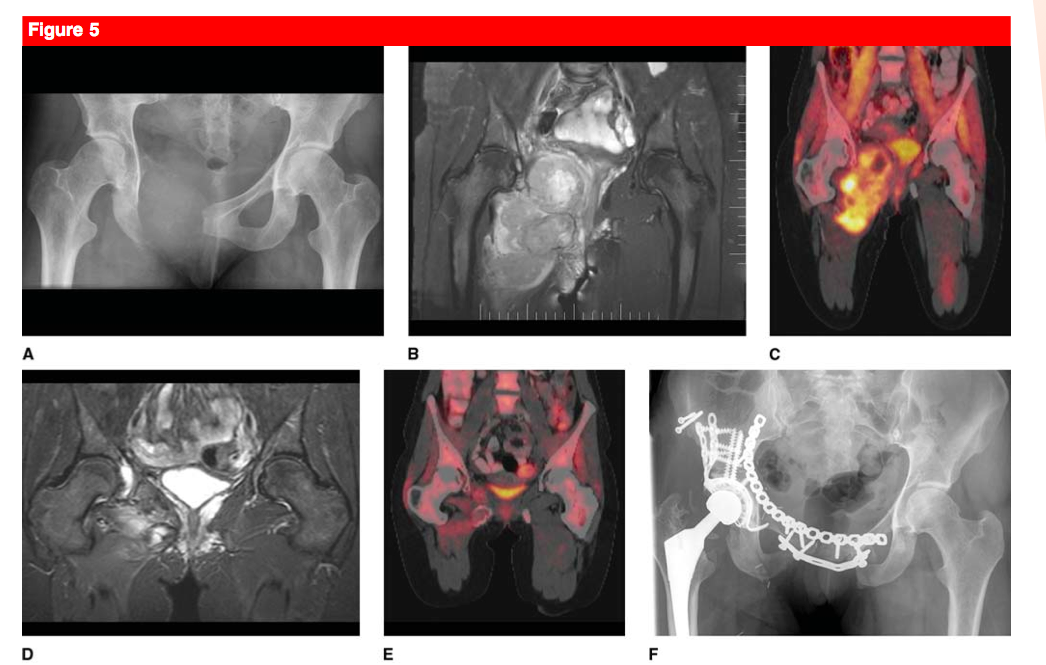

Describe the XR. Differential? Managment?

Malignant Fibrous Histiocytoma

Differential for multiple lesions in a young adult

EG

Fibrous dysplasia

Leukemia

Lymphoma

Hemangioendothelioma

Enchondroma / Olliers / Marfucci’s

Osteochondroma / MHE

NOF / Jaffe-Campanacci syndrome